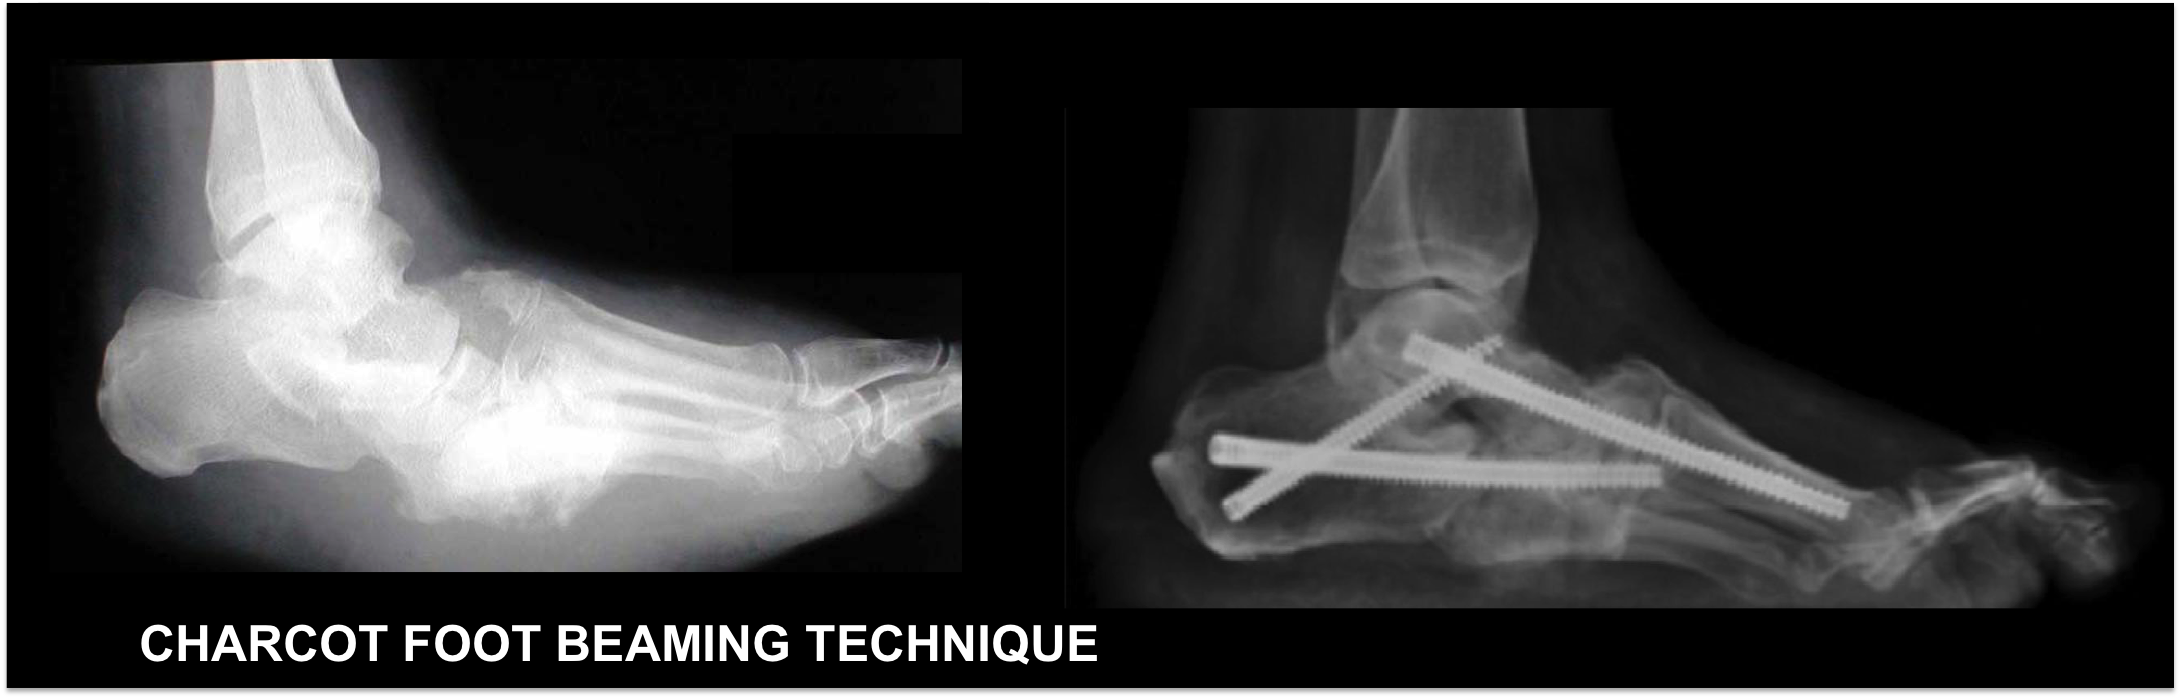

This first picture below show a typical midfoot charcot on the left with its post-operative appearance on the right. You can see the larger screws placed across the foot to hold all of the fragments in place.